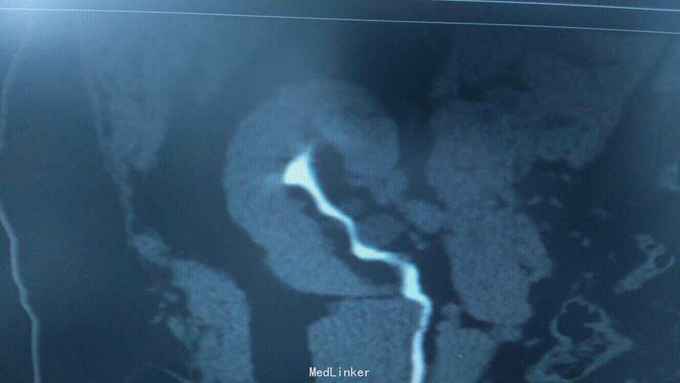

68岁,女性。 主诉:左侧腰痛1年,加重1个月。 病史:1年前无明显诱因出现左侧腰痛,无恶心呕吐,无肉眼血尿。1个月前加重,于外院查泌尿系彩超显示:左肾积液,输尿管显示不清。

诊断:双肾盂旁囊肿 治疗:因患者肾盂未明显受压,疼痛症状不明显,等待观察,暂未予处理。

双侧同时出现的病例并不多见,临床只能通过泌尿系统CTU或增强CT加以鉴别,彩超无法区分肾盂积水及盂旁囊肿。